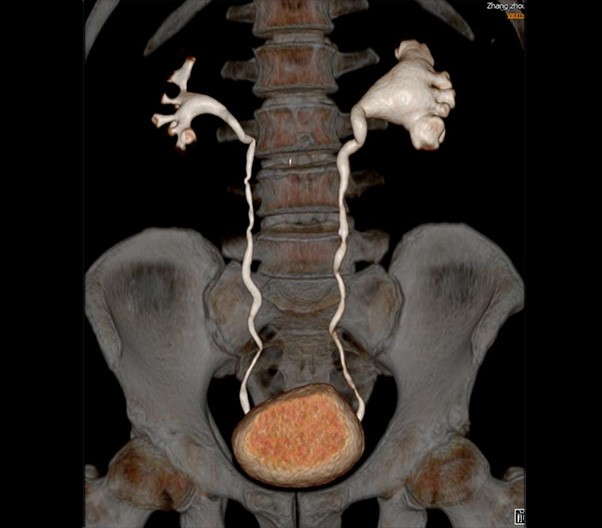

臨床畫廊